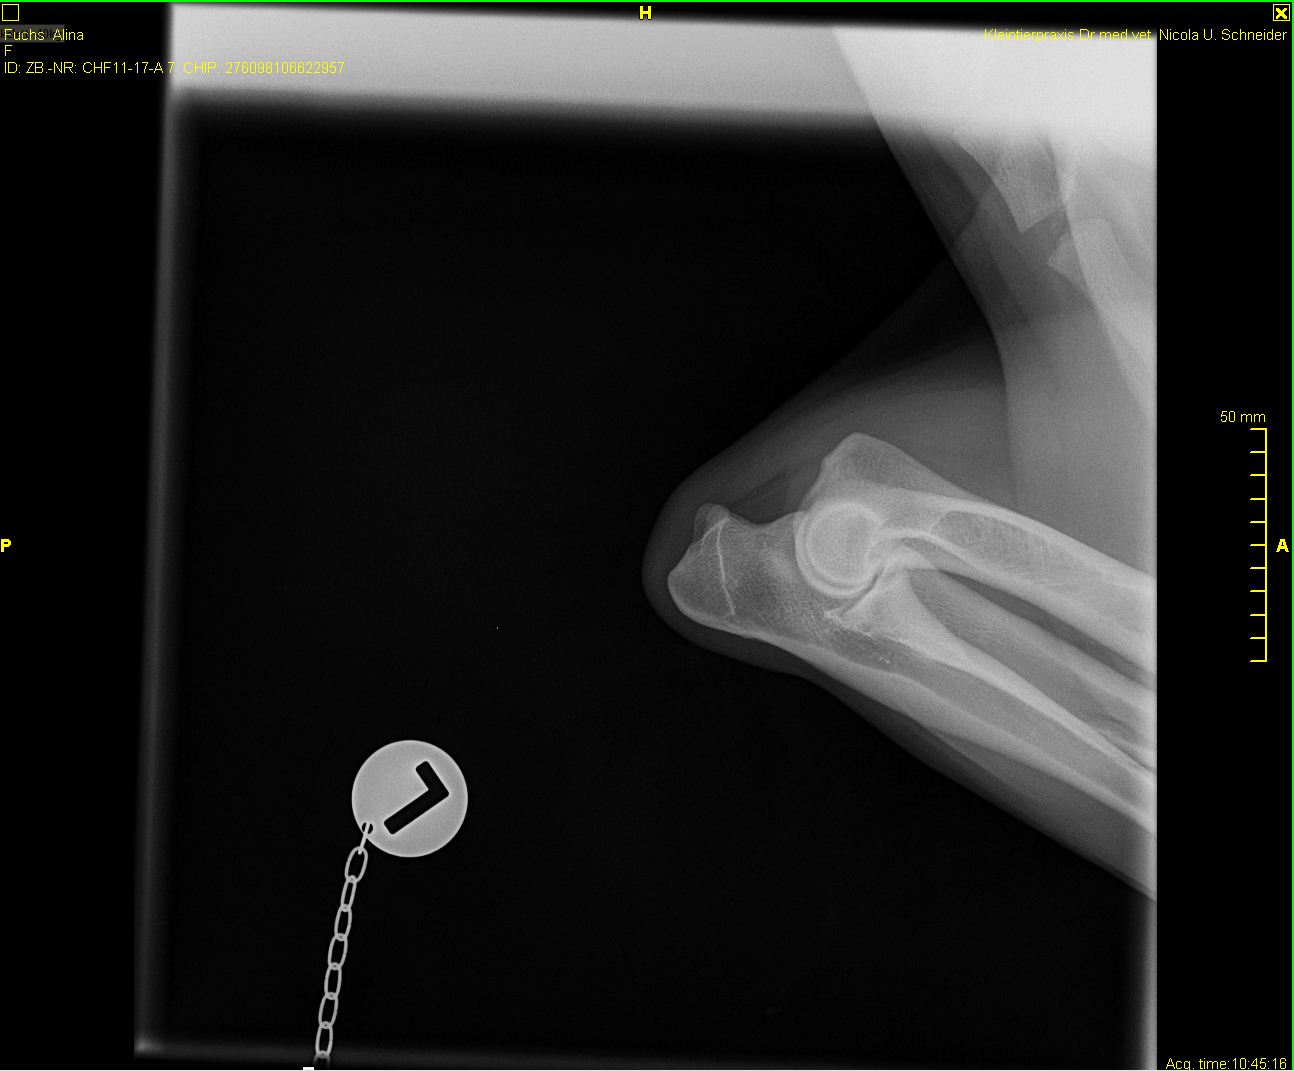

Alina - ED-Röntgen

-Alina-ed-rechts